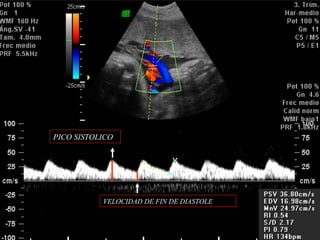

PICO SISTOLICO

VELOCIDAD DE FIN DE DIASTOLE

ANORMALIDADES DEL CORDONUMBILICAL (NUDO) PICO SISTOLICO VELOCIDAD DE FIN DE DIASTOLE